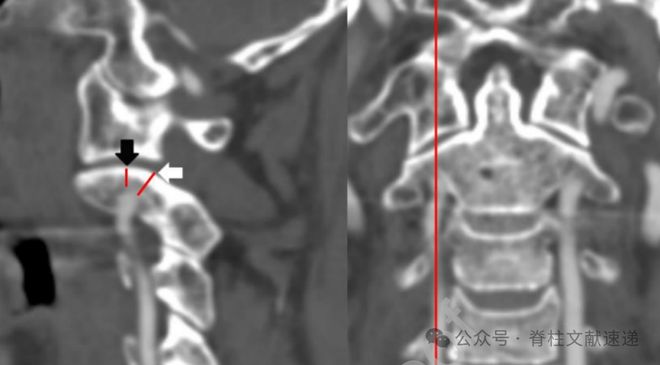

作者采用的是在椎管内壁旁开3mm处的矢状面,C2峡部高度(虚线侧块内部高度(实线 mm。和常用的冠状面侧块中点处的矢状面测量相似(再下图)。

1型——C2峡部高度≤5 mm,C2侧块内部高度在正常范围内(2 mm)。

2型——C2峡部高度在正常范围内(5 mm),C2侧块内部高度减少≤2 mm。。